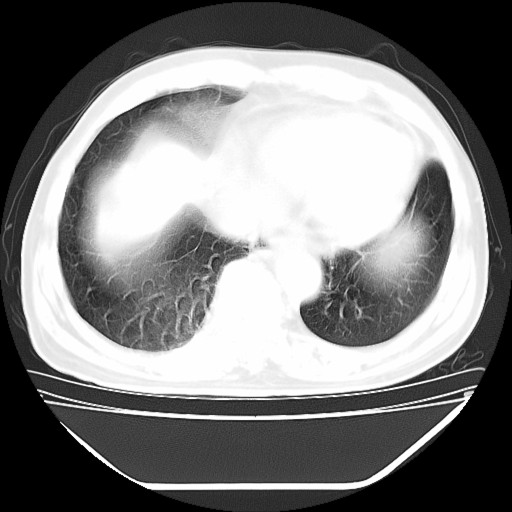

以下是引用hhcckk在2009-5-29 10:34:00的发言:[br]左下肺片絮状边缘模糊影,考虑感染,建议治疗后复查[br]